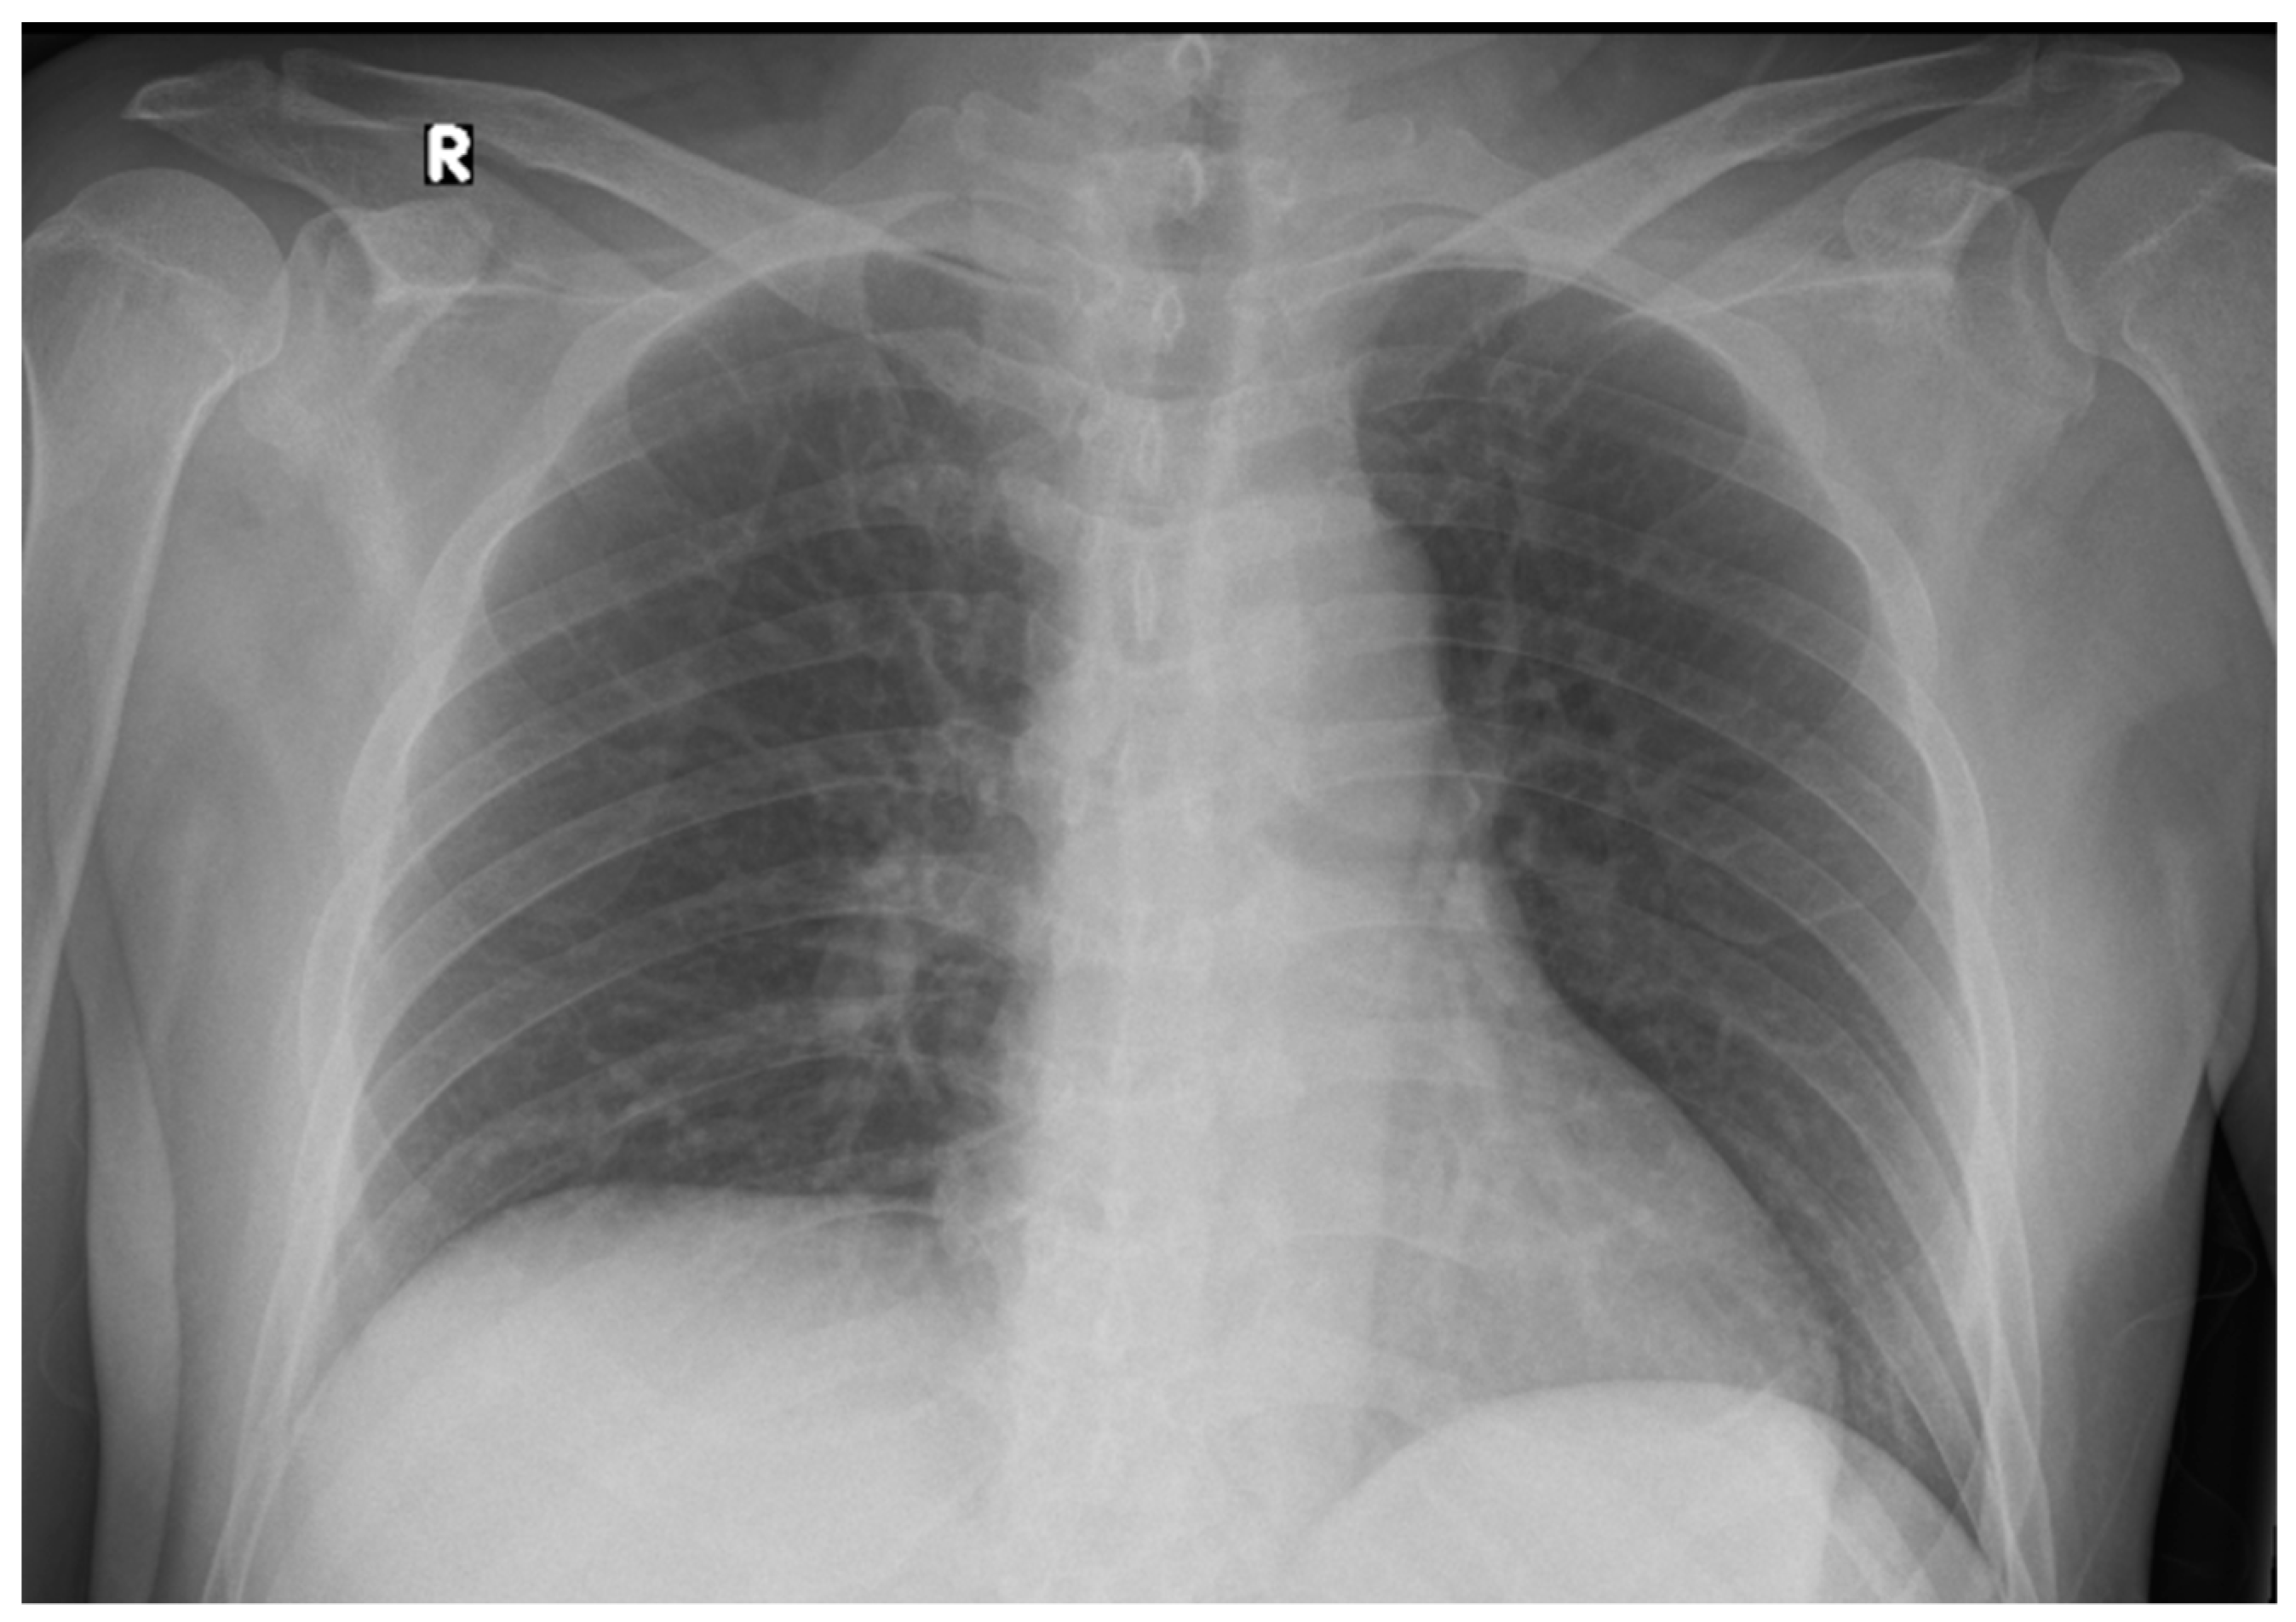

2. Case Presentation